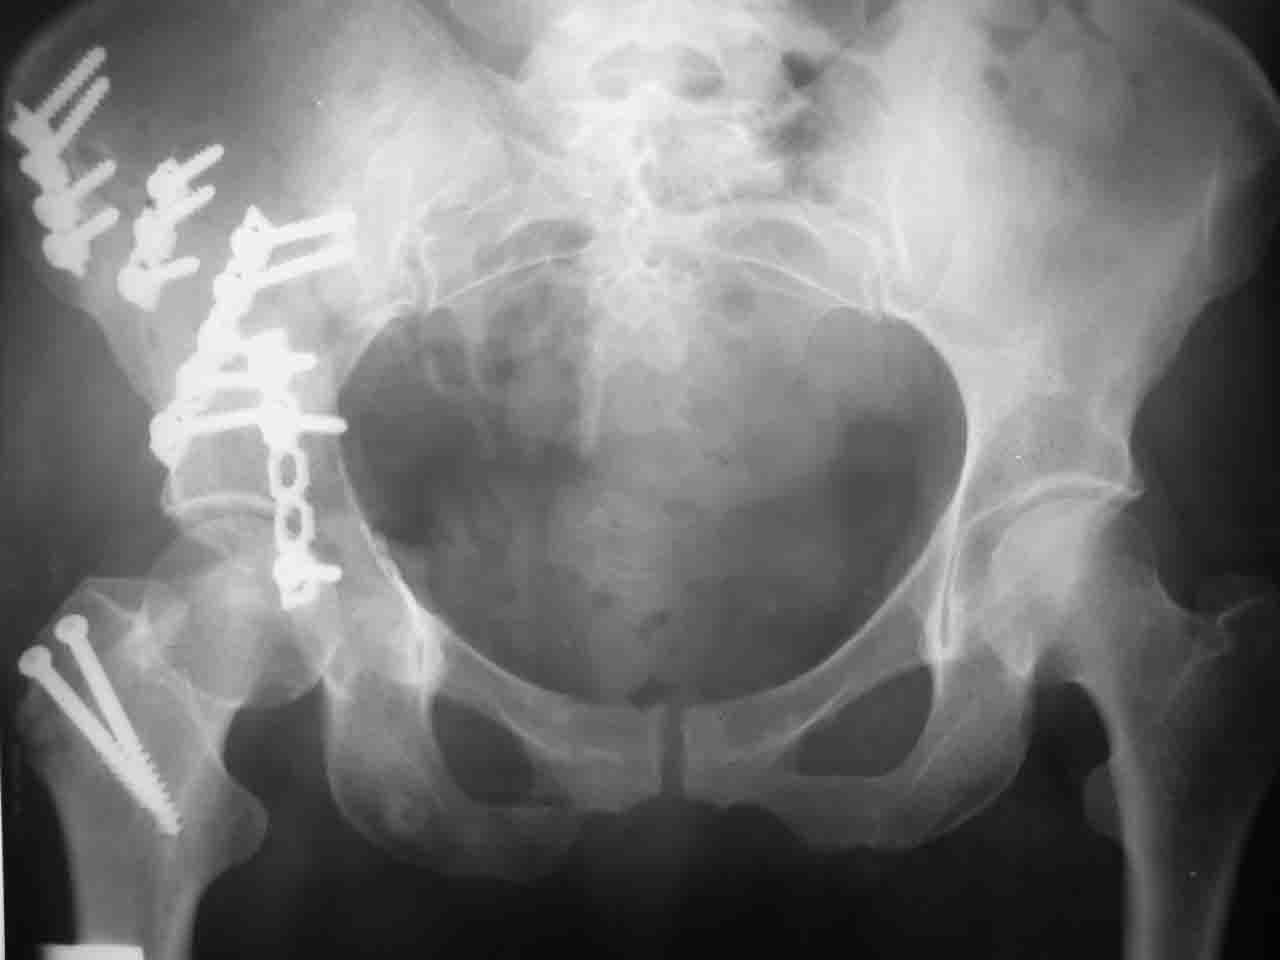

Сложностью, ассоциативностью характера перелома, я бы с радостью воспользовался мининвазивной перкутанной фиксацией винтами, но боюсь, что результат был бы ещё хуже, техникой непрямой репозиции перелома не владею, поэтому пытаясь получить анатомичную впадину приходится широко открывать, по крайней мере пока, а дальше буду пытаться уменьшать пространство...

Илеофеморальный доступ не совсем передний и сравнительно с илеоингвинальным, и Кохера-Лангенбека открывает весь наружный таз кроме самых передних отделов лонных костей, фиксацию которых я не ставил в задачу. Обширность диссекции, большая длительность операции и более высокий риск гетерооссификации - отрицательные моменты в обмен на возможность легче ориентироваться.

Вопрос доступа к вертлужной впадине при остеосинтезе задача не простая. Конечно, у Летурнеля и Тайла всё давно описано, нам остается только брать на вооружение. Но сами понимаете, что не бывает двух одинаковых ситуаций, поэтому в каждом случае вопрос решается сугубо индивидуально. Наша главная цель - восстановить анатомию с нанесением минимальной дополнительной травмы тазобедреннному суставу, думаю с этим никто не поспорит. Расширенный илиофеморальный доступ уж слишком травматичен (как сказал один коллега "таз лежит отдельно, больной отдельно").Стоит ли делать из пациента анатомический препарат для того чтобы легче ориентироваться. Да и нужно ли собирать всю "мозаику"? Мы применяли при таких операциях своеобразную операционную хитрость - сначала устраняли грубое смещение крыла под гребнем с фиксацией так называемой "плавающей" пластиной (временно фиксированной на двух винтах)- доступ или продлевали боковой, или делали небольшой дополнительный разрез над гребнем. Это позволяло устранить грубое смещение и захождение отломков тела повздошной кости, что значительно облегчало репозицию и остеосинтез впадины над сводом. Основное внимание конечно же уделяли нагружаемому задне-верхнему отделу. Сообщите ваш адрес, пришлю схемы и рентгенограммы.